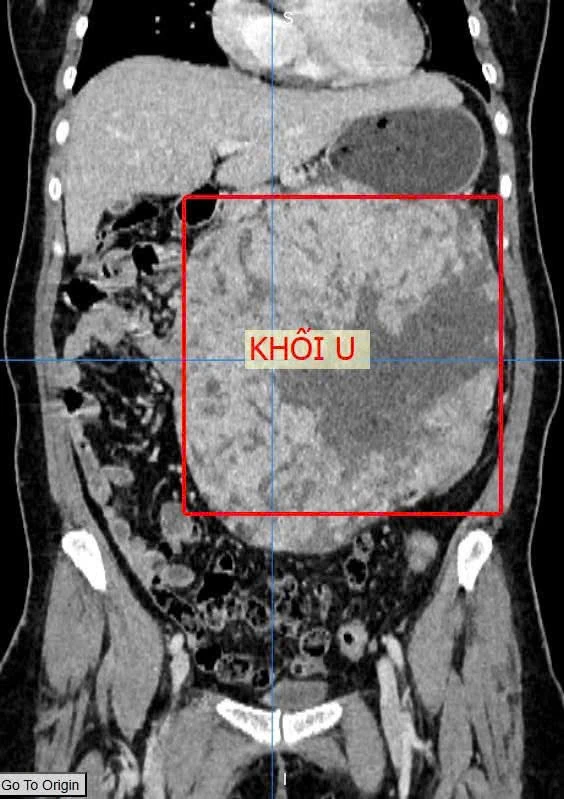

Kết quả xác định bệnh nhân có khối u lớn, kích thước 20x18x13 cm, nghi ngờ u GIST (khối u mô đệm đường tiêu hóa) xuất phát từ dạ dày.

Khối u lớn, kích thước 20x18x13 cm. Ảnh: BVCC

Nhận định đây là ca bệnh phức tạp, khối u chiếm 50-60% thể tích ổ bụng, có đặc điểm tăng sinh mạch máu nuôi nhiều, các bác sĩ quyết định phẫu thuật mở để đảm bảo an toàn tối đa trong quá trình bóc tách và kiểm soát chảy máu.